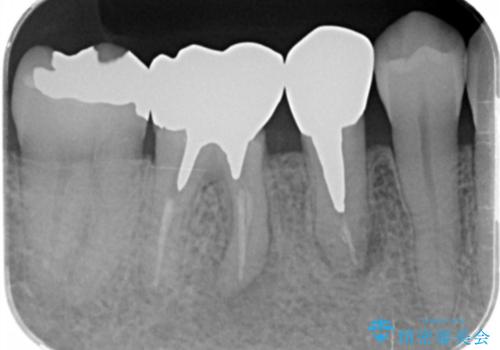

- 食事のたびに、銀歯の間や周囲に食ベカスが挟まったり溜まったりすることの改善を求めて来院されました。

銀歯の形状に問題があり、食べかすの詰まりやすい状況を、精度の高いセラミッククラウンに置き替えることで不快症状の改善を計画します。